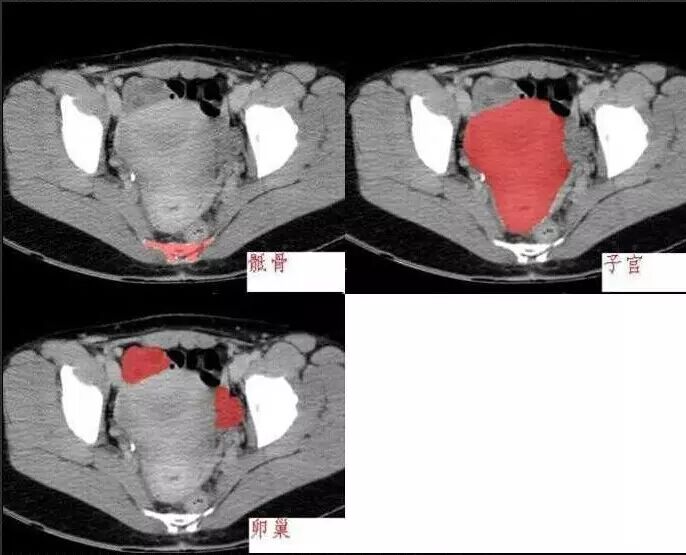

十分钟学会腹部CT解剖(多图)